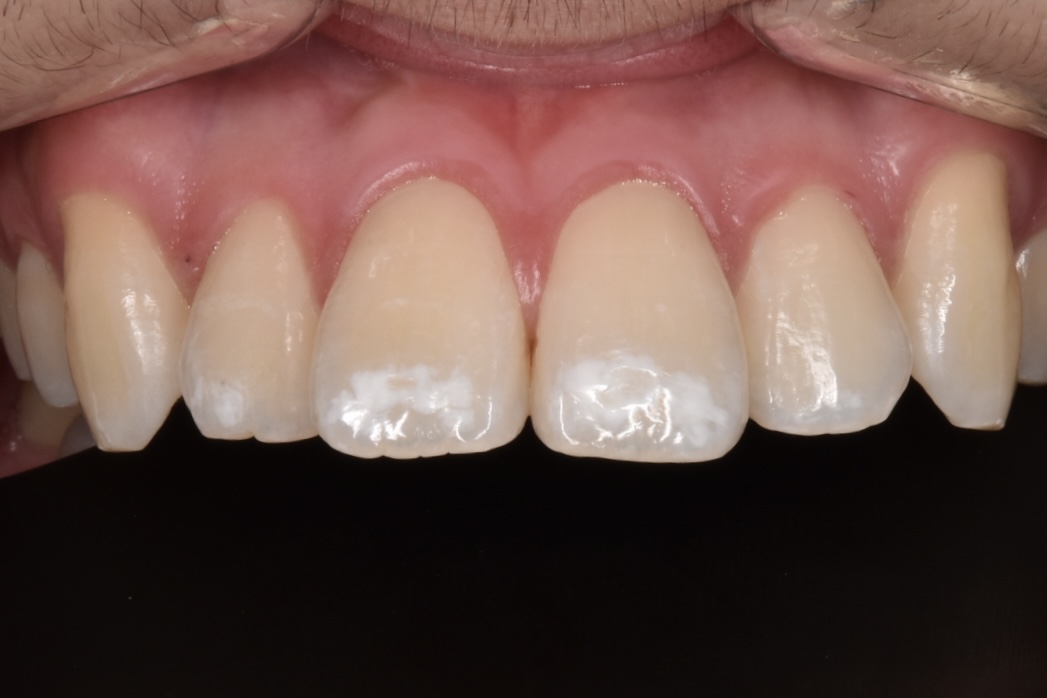

40代女性他院セラミックの修正治療

モニター様ご紹介 20年ほど前に他院で受けたセラミック治療をした歯のお痛みがあるのと、治した歯の周囲が黒く目立つので改善したいとご相談くださいました。当院に通ってくださっている方からのご紹介です。 初診時の状態 他院セラミックの上の歯茎が痛いという症状があったのでレントゲン撮影とCT撮影をしています。前歯の根の先に黒い影が見えます。これは根の先に膿が溜まって …